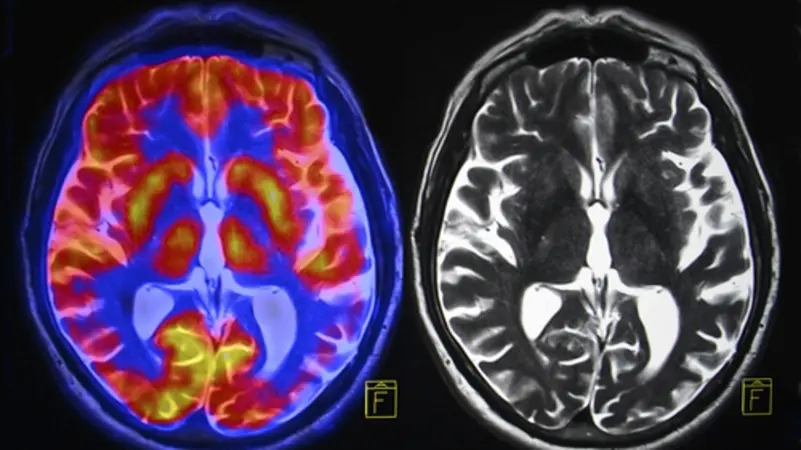

السوسنة - توصل فريق من الباحثين إلى طريقة جديدة لقياس سرعة الشيخوخة البيولوجية لدى الإنسان، باستخدام صورة واحدة للدماغ عبر تقنية التصوير بالرنين المغناطيسي، وفقًا لدراسة نُشرت في دورية "Nature Aging" ونقلها موقع "Live Science".

وأوضح الباحثون أن هذه الأداة الجديدة تتيح التنبؤ بمخاطر الإصابة المستقبلية بضعف الإدراك والخرف والأمراض المزمنة، مثل أمراض القلب والسكري والوفاة المبكرة، بناءً على تحليل بنية الدماغ.

وحلل الباحثون صور الرنين المغناطيسي المأخوذة في سن 45 عامًا، ودرسوا حجم وسمك مناطق الدماغ المختلفة ونسبة المادة البيضاء إلى الرمادية، باستخدام خوارزمية تعلم آلي. ثم قارنوا هذه البيانات بمؤشرات التدهور البدني والإدراكي، وسمات الوجه المرتبطة بالشيخوخة، مثل التجاعيد.

وأطلق الفريق على النموذج الجديد اسم "سرعة دنيدن للشيخوخة المحسوبة من التصوير العصبي"، وهو امتداد لأداة سابقة طوّروها باسم DunedinPACE، التي تعتمد على تحليل الميثلة – وهي علامات كيميائية ترتبط بجزيئات الحمض النووي – لتقدير وتيرة الشيخوخة.

وأكد الباحثون أن النموذج الجديد يمكن استخدامه حتى في غياب البيانات الجينية، مما يفتح المجال أمام تطبيقه في دراسات واسعة النطاق. وقد اختُبر النموذج على أكثر من 42 ألف صورة دماغية من البنك الحيوي البريطاني، و1700 صورة من مبادرة التصوير العصبي لمرض الزهايمر، و369 صورة من مجموعة BrainLat في أميركا الجنوبية، وأثبت دقة مماثلة للمقاييس السابقة.